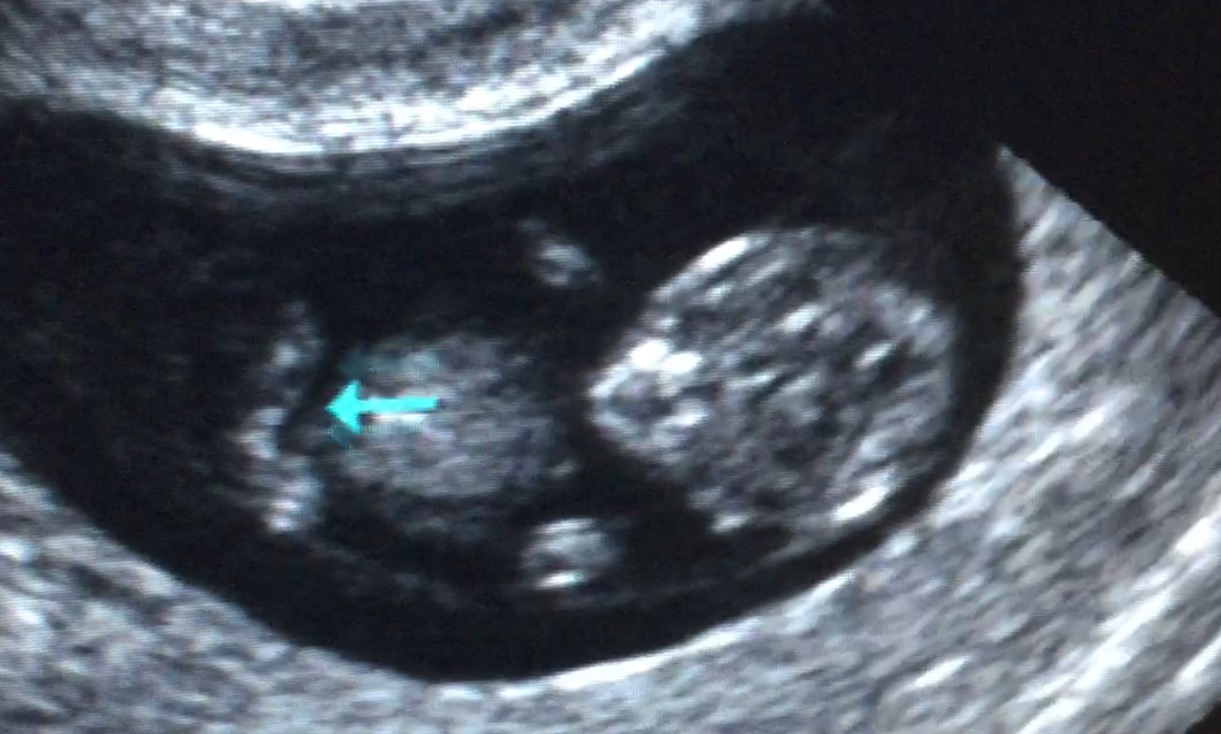

Those 2 nubs are "its" legs and I can't tell whatever is in between there?!

One more photo of the nub... I don't know which angle this it taken from.

11 weeks is too soon to tell, I'm afraid. They both look pretty much the same at this gestation.

Am I seeing things or can I see the cutest little toes in this scan pic :heart: